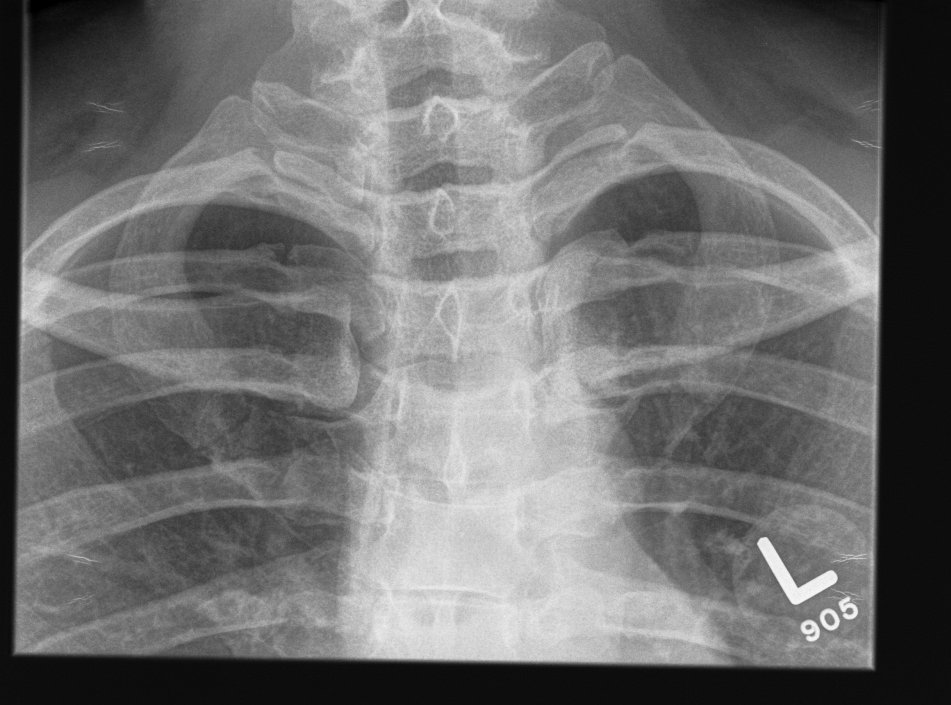

Xray

- sclerotic and overgrown